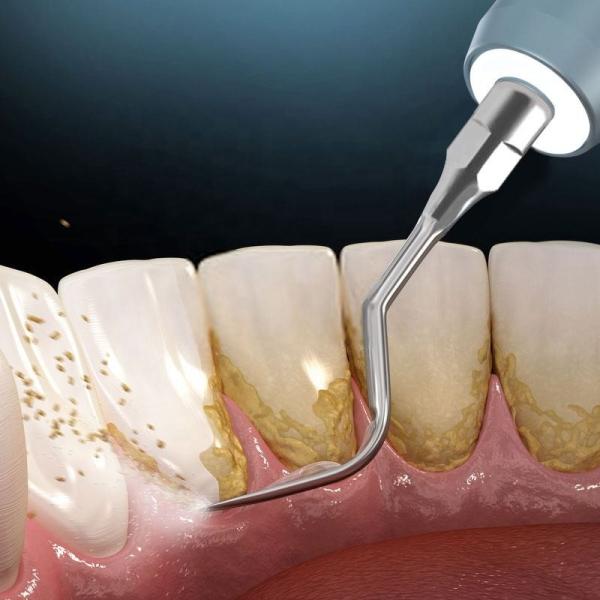

Intelligent Aotumatic Smart Dental Ultrasonic Scaler And Supragingival And Subgingival Polisher

Multiple function

With different scaler tips, the machine is applicable to implant maintenance, broken file removing,

gutta-percha cutting, crown removing, cavity preparation, shoulder preparation, calcifications removing

and root planning.

Teeth Cleaning Ultra Sonic Scaler Machine Multifunctional Durable Images |